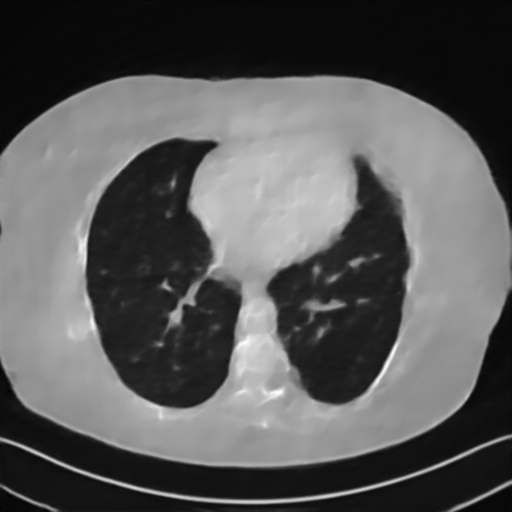

Fig. 7 manifests the reconstruction results of these methods with scanning angular of . It can be seen that both FBP and FBP-Unet produce serious artifacts within the range of missing angles. The TV model performs well in removing Poisson noises, but it can not handle the artifacts very well. Similarly, there left obvious artifacts on boundaries and different degrees of missing in visceral tissues of the reconstruction images obtained by the SIPID, PD-net and FSR-net. The visceral tissue and boundaries of our LRIP-net reconstructions are more intact and smoother, especially for the LRIP-net1/8 which gives the ideal boundaries. The observation becomes even apparent if we look at the zoom-in regions, where the LRIP-nets can produce results with fine structures. Therefore, we conclude that the low-resolution image prior can effectively improve the qualities of the limited-angle CT reconstruction.